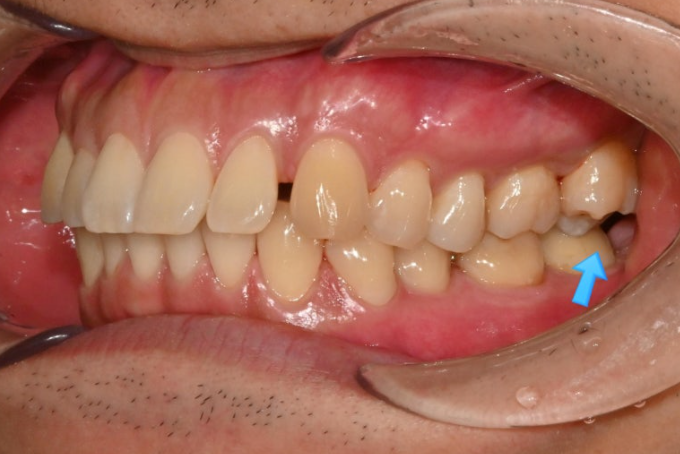

파란 화살표와 같이 물리는 상태를 가위교합이라고 합니다.

맨 뒤 큰 어금니에 흔하게 보이는 부정교합입니다.

위 어금니는 배열에서 바깥으로 나가있고

아래 어금니는 안으로 쓰러져 있습니다.

가위교합의 빠른 해결을 위한 입천장의 교정용 나사도 썼습니다.

안으로 쓰러져 있던 큰어금니도 잘 세워졌고 가위교합도 해소가 되었습니다.